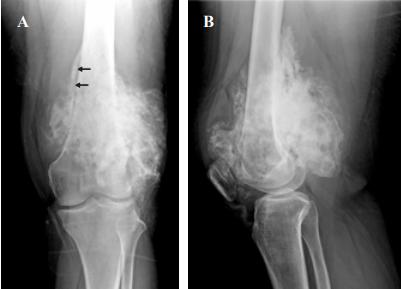

左膝正位片和侧位片显示一个外生的分叶状骨肿瘤,主要附着于骨干远端三分之一和股骨干远端后表面。肿瘤呈中心致密骨化,肿瘤与下骨间呈薄透光带(图1)。

图1、左膝正位片(A)和侧位片(B)。分叶和外生性骨肿瘤,中心致密骨化,主要毗邻骨干远端三分之一的后表面和股骨干远端。肿瘤与相邻的正常皮层(绳索的标志)之间可见透光分裂(箭头),在组织学上对应于皮层与肿瘤肿块之间的骨膜